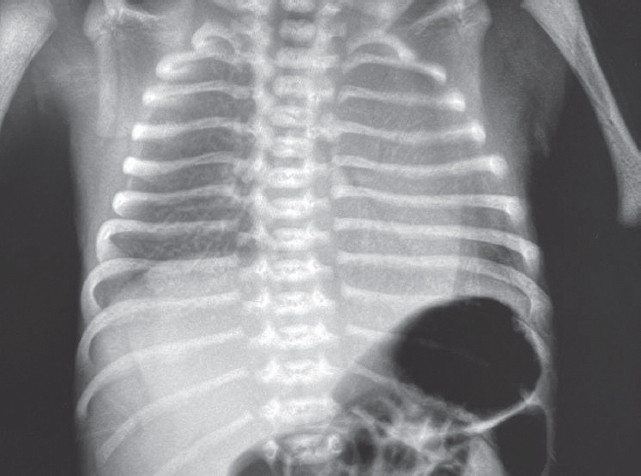

На этом фоне отмечается выраженный положительный эффект в виде увеличения SpO2 с 7–23 до 90 %, на контрольной рентгенограмме сразу после введения порактанта альфа (рис. 3) отмечается незначительное улучшение пневматизации левого легкого, сохраняется свободный воздух в правой плевральной полости.

Рис. 3. Рентгенограмма органов грудной клетки новорожденного после монобронхиального введения сурфактанта

Fig. 3. Chest X-ray of newborn after monobronchial surfactant administration

На контрольной рентгенограмме через 6 ч после манипуляции сохраняются признаки правостороннего пневмоторакса, отмечается неравномерное восстановление воздушности левого легкого. Снизить параметры ВЧО ИВЛ не представлялось возможным. В последующем отмечено прогрессирование явлений дыхательной недостаточности с десатурацией (SpO2 46 %), по анализу газового состава венозной крови отмечается выраженная венозная гипоксемия (рО2 13 мм рт. ст.), гиперлактатемия (6,7 ммоль/л). Сохраняется выраженная артериальная гипотензия, в связи с чем скорость введения адреналина увеличена до 0,2 мкг/(кг · мин), на этом фоне достигнута стабилизация.